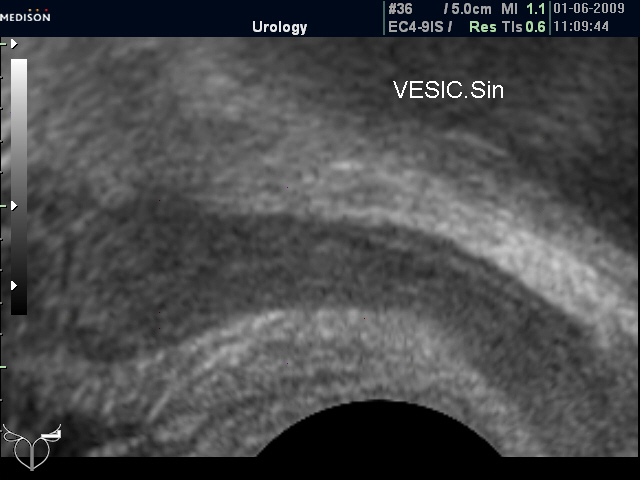

Нормальные семенные пузырьки при ТА и ТР УЗИ (фото 1 и 2).

Нормальные СП (ТР УЗИ)